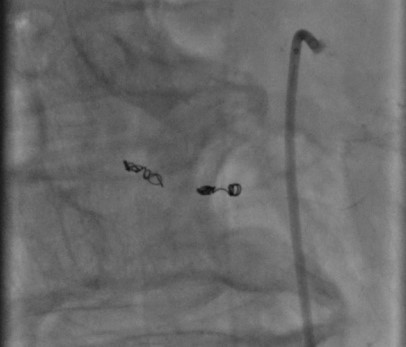

В данную госпитализацию, 12.10.2021 г., пациенту выполнена ангиография: определяется неровность контура средней трети ветви второго порядка нижней панкреатодуоденальной артерии с формированием мешотчатой аневризмы 3х5 мм (рис. 3). По результатам выполненной ангиографии, пациенту показано выполнение эмболизации ветви нижней панкреатодуоденальной артерии в плановом порядке.

Для выполнения планового оперативного лечения пациент повторно госпитализирован 22.11.2021 г. в клинику СЗГМУ им И.И. Мечникова. 25.11.2021 г. была предпринята попытка эмболизации второй ветви нижней панкреатодуоденальной артерии с аневризмой из лучевого доступа слева. В связи с изгибом верхней брыжеечной артерии в месте отхождения панкреатодуоденальной артерии, завести коронарный проводник технически было невозможно (рис. 3). Учитывая большой объем введенного контрастного вещества, длительность операции, принято решение выполнить эмболизацию нижней панкреатодуоденальной артерии.

Рис. 3. Ангиография верхней брыжеечной артерии.

Fig. 3. Angiography of the superior mesenteric artery.